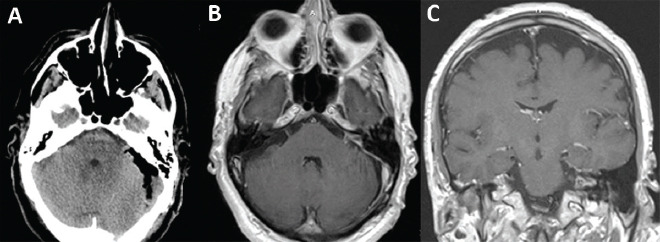

Objective: Anticoagulant therapy is a risk factor for repeated intratumoral hemorrhage and acute enlargement of a vestibular schwannoma (VS) with neurological deficits. Therefore, we describe two cases of patients on oral anticoagulant therapy with intratumoral hemorrhage in which anticoagulant therapy prior to surgical resection was discontinued. We also discuss other similar cases from the literature since this is a rare event.

Case reports: We described the two cases of intratumoral hemorrhage in acoustic neurinoma and conducted a literature review of similar cases of patients with intratumoral hemorrhage in acoustic neurinoma who were also on oral anticoagulants. Both patients presented with CN-VII palsy prior to surgery; both also fully re-covered after surgery except for hearing loss on the tumor side. Our literature review found 50 cases of VS (reported as vestibular schwannomas in the literature) with intratumoral hemorrhage. From this total, 11 patients used oral anticoagulant therapy with reported poor outcomes and high mortality; 9 of these 11 cases were reported in the past 20 years. The incidence is expected to rise due to increased use of anticoagulant therapy due to onset of atrial fibrillation, atherosclerosis, and thromboembolism from longer human lifespan.

Conclusion: Anticoagulant therapy represents a risk factor for intratumoral hemorrhage and acute enlargement of VS tumor mass with neurological deficits.